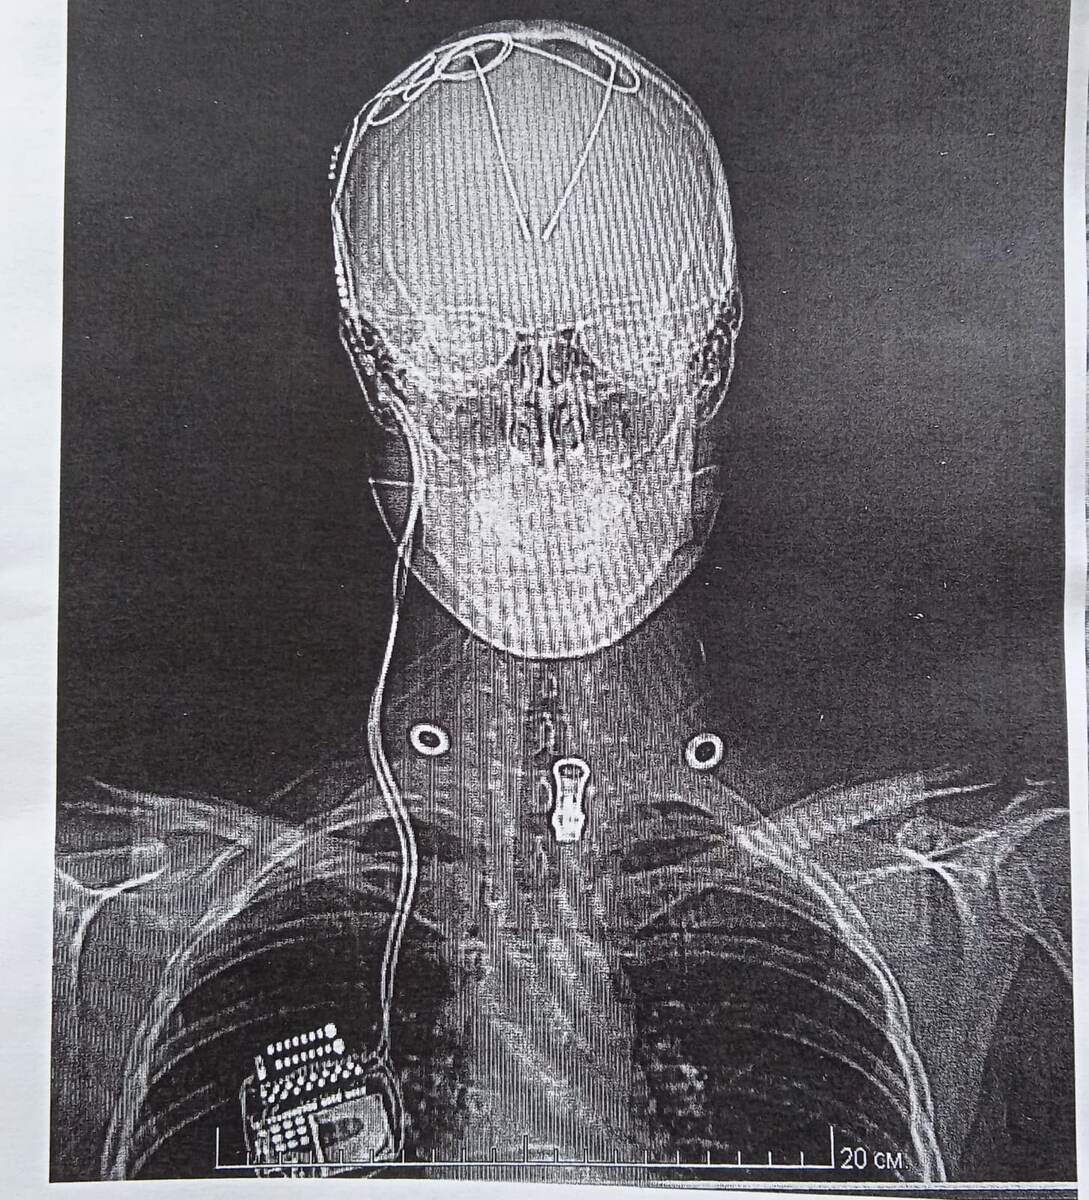

Представьте: Бритая на лысо голова... 21 титановая скоба, сжимающая череп. 140 сантиметров провода, вживлённого в мозг и спускающегося по шее, под кожей, к коробочке-стимулятору под ключицей. Шрамы. И ты идёшь по улице... Люди пялятся. Дети пугаются. Взрослые шепчутся. В метро уступают место – не из вежливости, а из жалости. Это бьёт по самооценке. Но я держусь: "Это временно. Я сильна. Я выжила". А если кто спросит: "Что это?" – отвечаю с улыбкой. Просвещаю. Пусть знают.

Глубокая стимуляция мозга (DBS) — нейрохирургический метод лечения резистентной к лекарствам эпилепсии, при котором имплантируемые электроды регулируют аномальную электрическую активность мозга. Процедура применяется, когда медикаментозная терапия неэффективна, а хирургическое удаление очага невозможно или нецелесообразно.